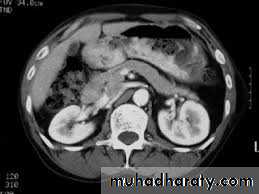

• US abdomen:size and thickness of cyst

• CT scan:size,shape,number,wall thickness,extent of necrosis,calcification,regional vessels

• MRCP and ERCP:communication with duct and ductal anomalies,chronic pancreatitis